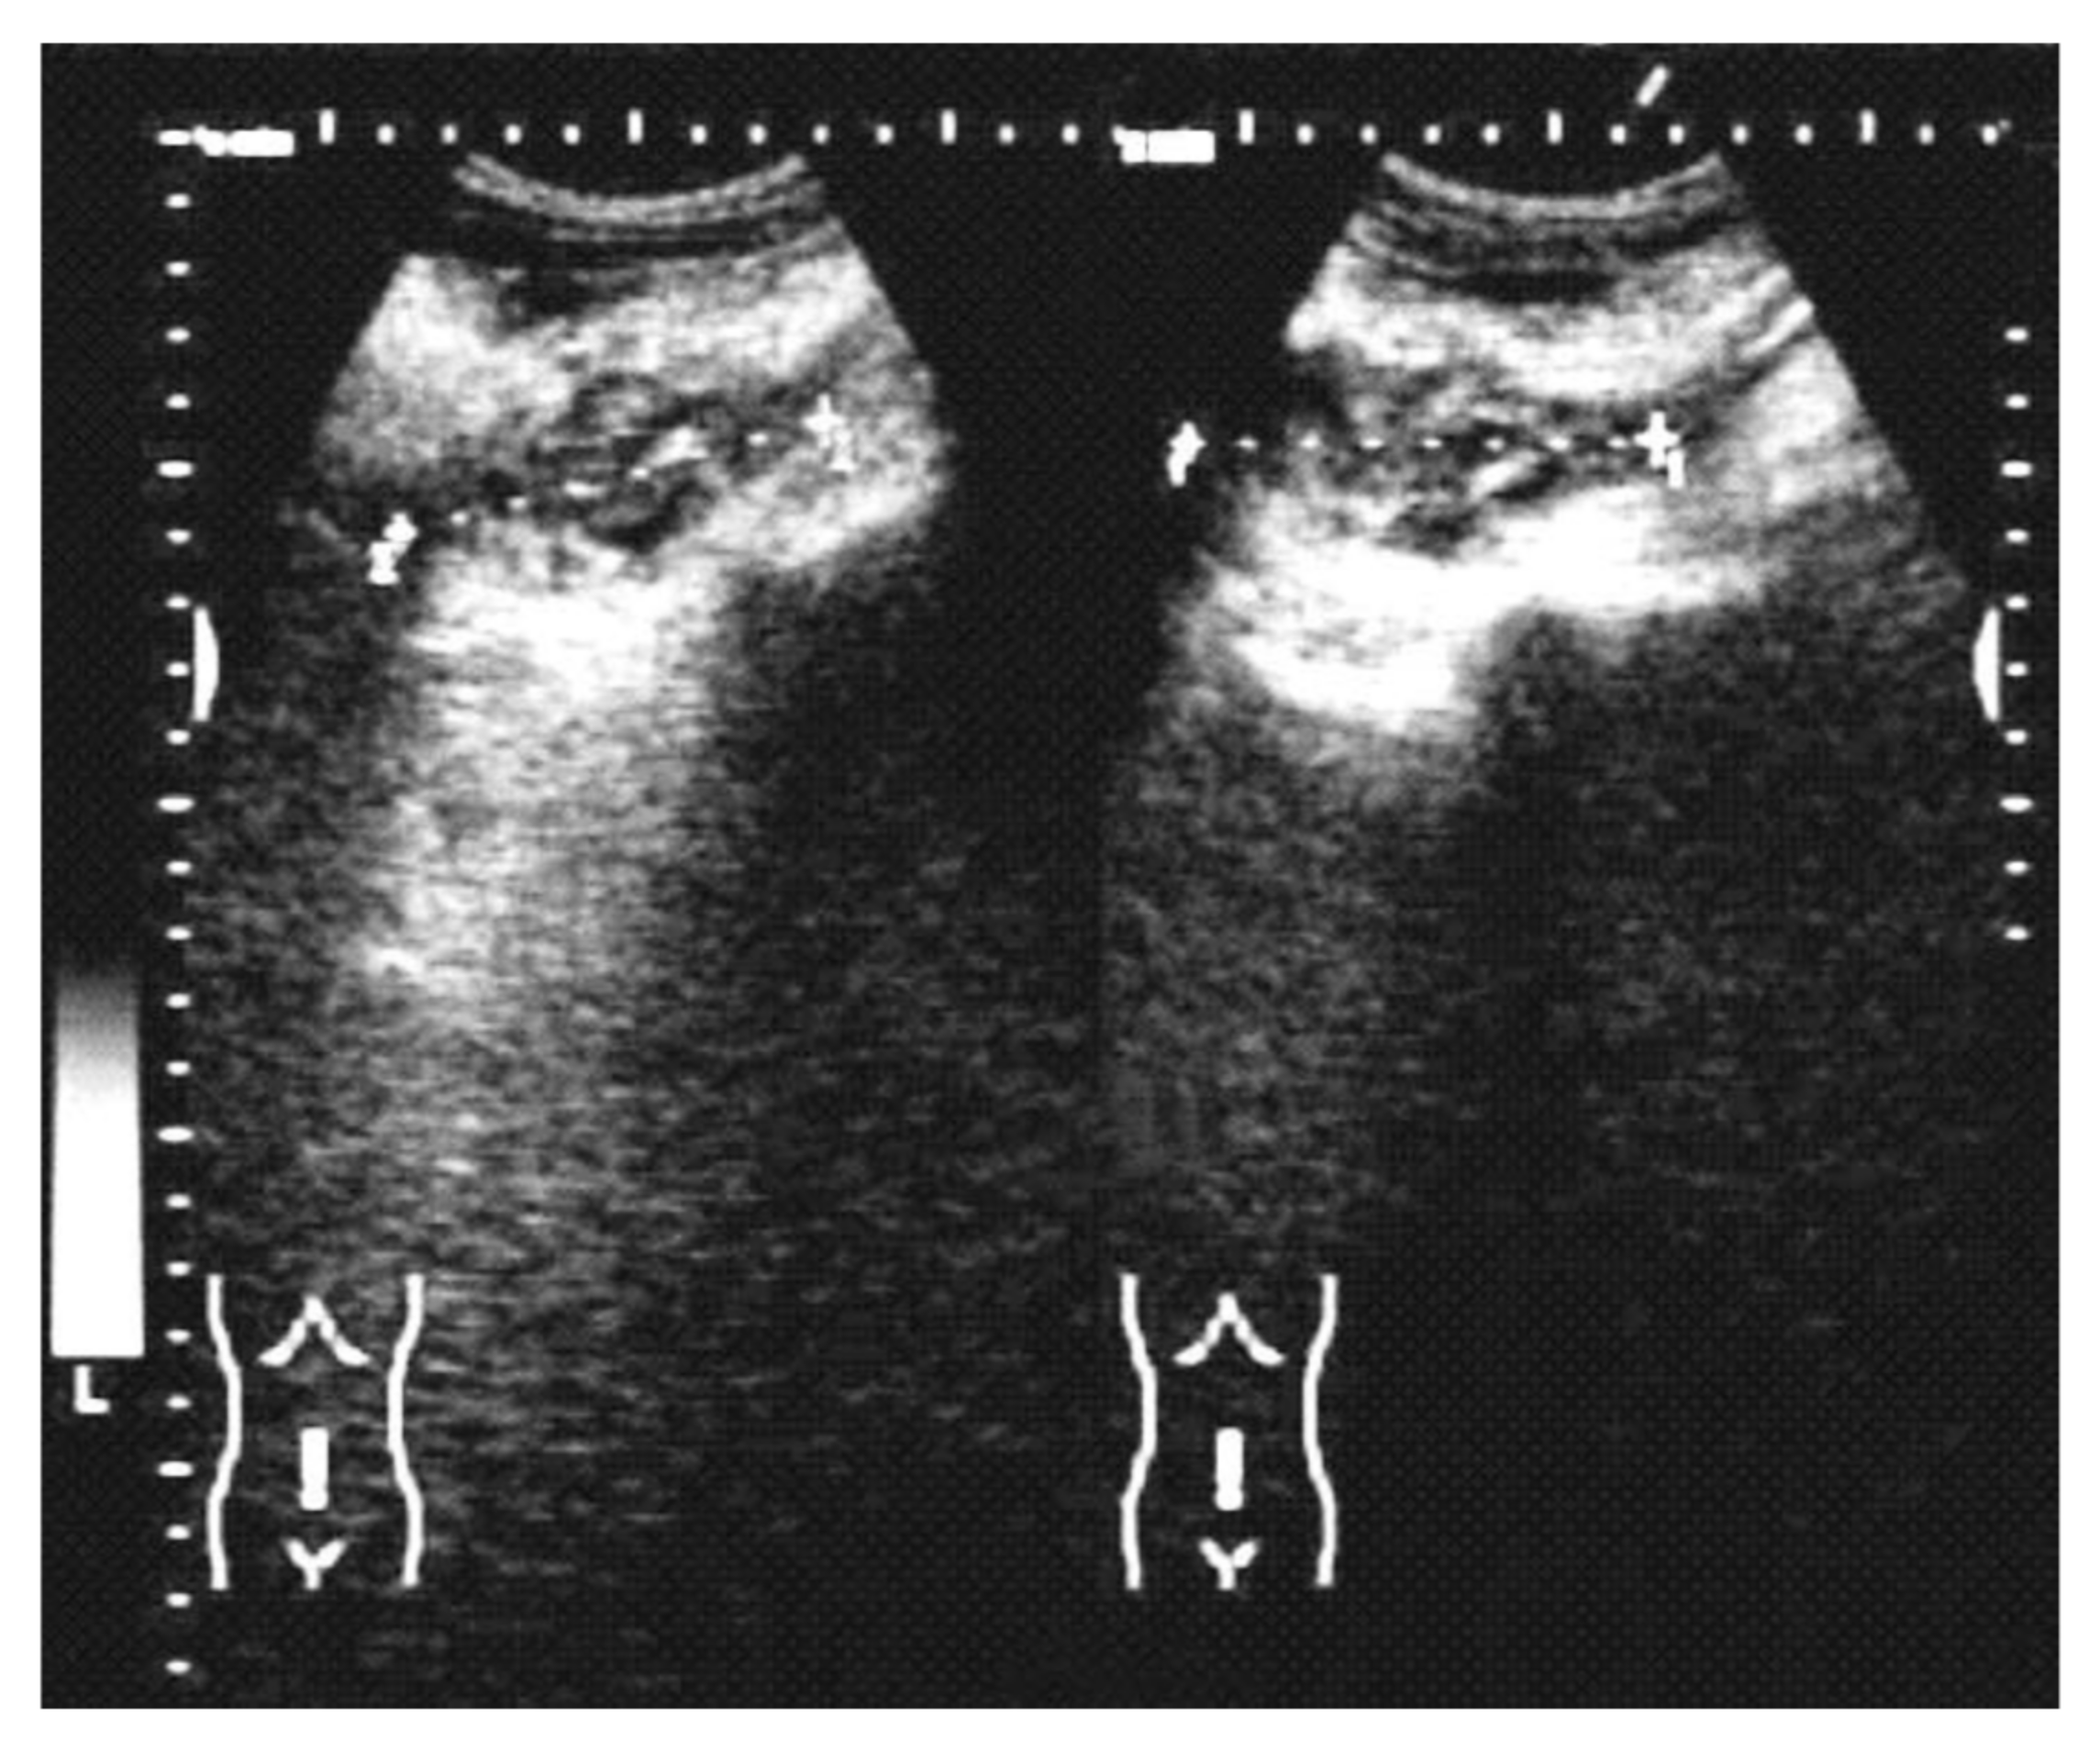

| Imaging (US, CT) characteristic | N (cases) (%) |

| Intraperitoneal collections | 11/28 (39.2%) |

| A heterogeneous mass involving the colon | 6/28 (21.4%) |

| Omental mass | 3/28 (10.7%) |

| Inflammatory mass involving the ovaries | 6/28 (21.4%) |

| Right liver abscesses | 2/28 (7.1%) |